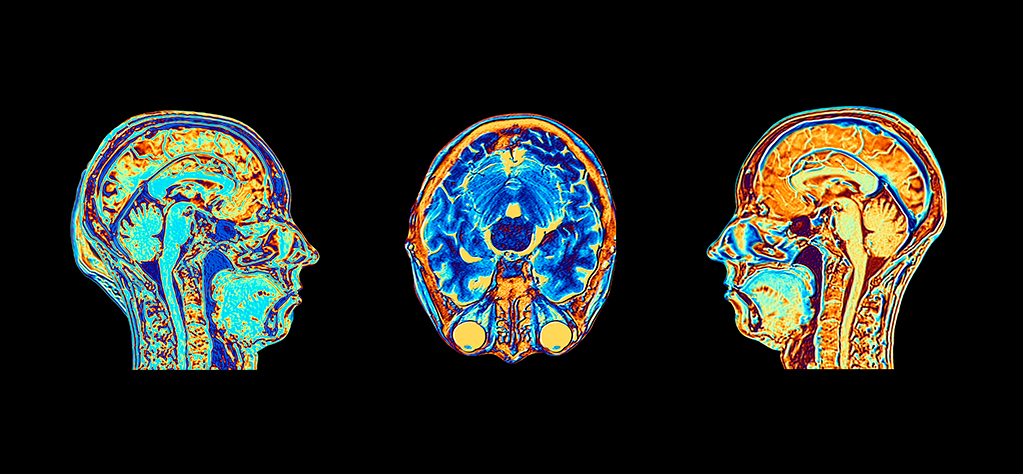

As Dr. Daniel Roberts explains, New England’s first Cranial Nerve & Brainstem Disorder Program brings together a multidisciplinary team of experts to streamline diagnosis and care for patients with these difficult conditions.